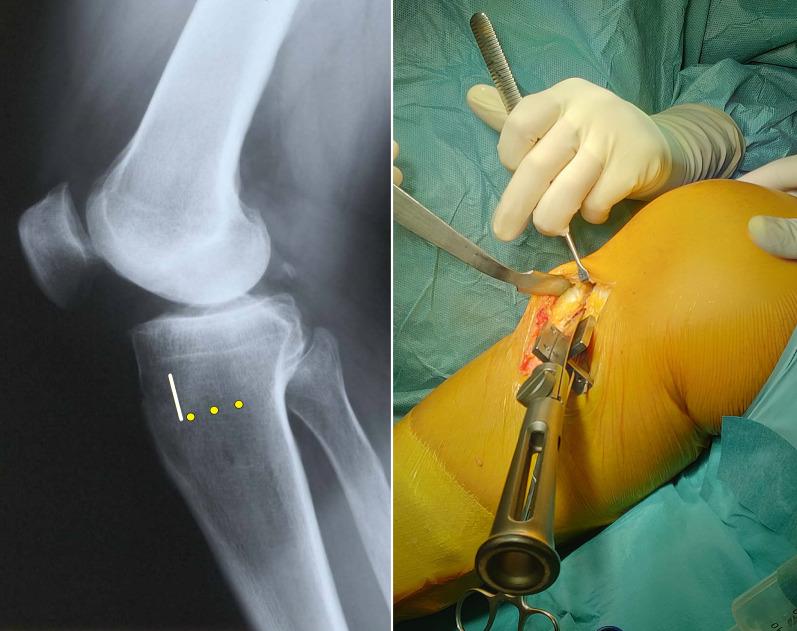

High tibial osteotomy (HTO) provides reliable and good long-term results, if performed with correct indications, but different techniques and types of fixation have been described. The purpose of this study is to present a novel modified biplanar medial opening-wedge (MOW) HTO technique where the osteotomies are performed in a Z-shaped fashion, and to present the medium-term clinical and radiographic results.

Modified biplanar Z-shaped MOWHTO is a safe and reliable technique that offers satisfactory clinical and radiological medium-term outcomes with low knee arthroplasty conversion rate. The unique three-dimensional geometrical conformation potentially provides a favorable environment for bone healing, increased anteroposterior and rotational stability, and safer opening-wedge loading force application with low lateral hinge fracture risk.

高胫骨截骨术(HTO)如果适应证选择正确,可提供可靠且长期良好的结果,但已描述了不同的技术和固定类型。本研究的目的是介绍一种新型改良的双平面内侧开口楔形截骨术(MOW)技术,其中截骨呈 Z 形,介绍中期临床和影像学结果。

改良的双平面 Z 形 MOWHTO 是一种安全可靠的技术,具有较低的膝关节置换翻修率,可提供满意的临床和影像学中期结果。独特的三维几何构形可能为骨愈合提供有利的环境,增加前后和旋转稳定性,并以较低的外侧铰链骨折风险安全地施加开口楔形加载力。